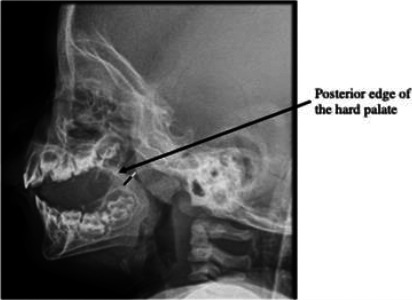

Interventions: Clinical information was obtained from the patient's medical records. Data was analysed for the clinical characteristics of the patients, the relationship between the degree of airway narrowing on a postnasal space (PNS) radiograph and treatment outcomes.

Main outcome measures: Degree of airway narrowing as measured on a PNS radiograph, the type of and outcomes of treatment.